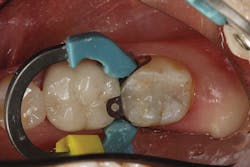

In terms of technique, isolation and standard tooth preparation for composite restorations are used. Using a sectional matrix technique provides the most predictable way to establish a solid and nicely contoured proximal contact.

The difference in using this product over standard- or non-bulk-fill composites comes in the filling technique. The manufacturer states that you can predictably cure an increment of this composite up to 4 mm in depth. This assumes the light energy coming from your curing light is ideally positioned and is functioning properly (power intensity of 1000 mW/cm2 or greater). For carious lesions that are relatively small to moderate in size (figures 1a and 1b), this translates, in general, to being able to place one increment of composite that fills partway up the proximal box to the level of the contact and onto the occlusal pulpal floor (figure 2). The second increment could then be placed on top, which would fill the rest of the restoration.

However, as mentioned earlier, getting the composite adapted to both the buccal and lingual cavosurfaces at the same time can be tricky. To address this, I have found it easier to place one increment of resin in a way that covers the entire buccal side of the preparation, including the marginal ridge area (figure 2), and light cure it prior to finishing the fill with the lingual increment. This requires one extra step, but it gives me the peace of mind that I am reducing the polymerization shrinkage on the opposing cavosurfaces as well as eliminating the back and forth nature of trying to adapt the composite to both sides of the cavity preparation (figure 3).